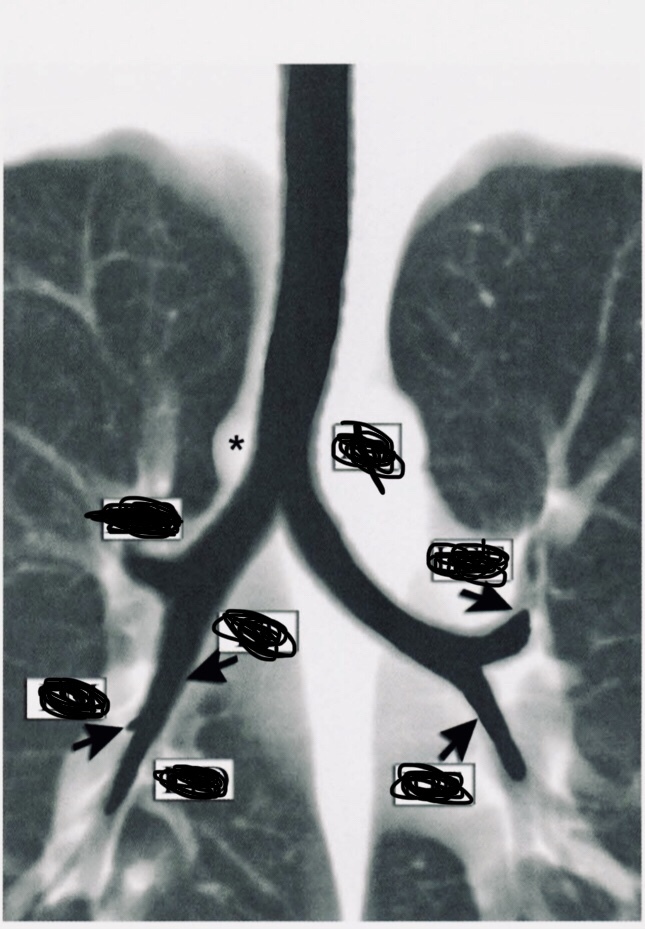

Descreva as fissuras apontadas pelas setas e os lobos pulmonares